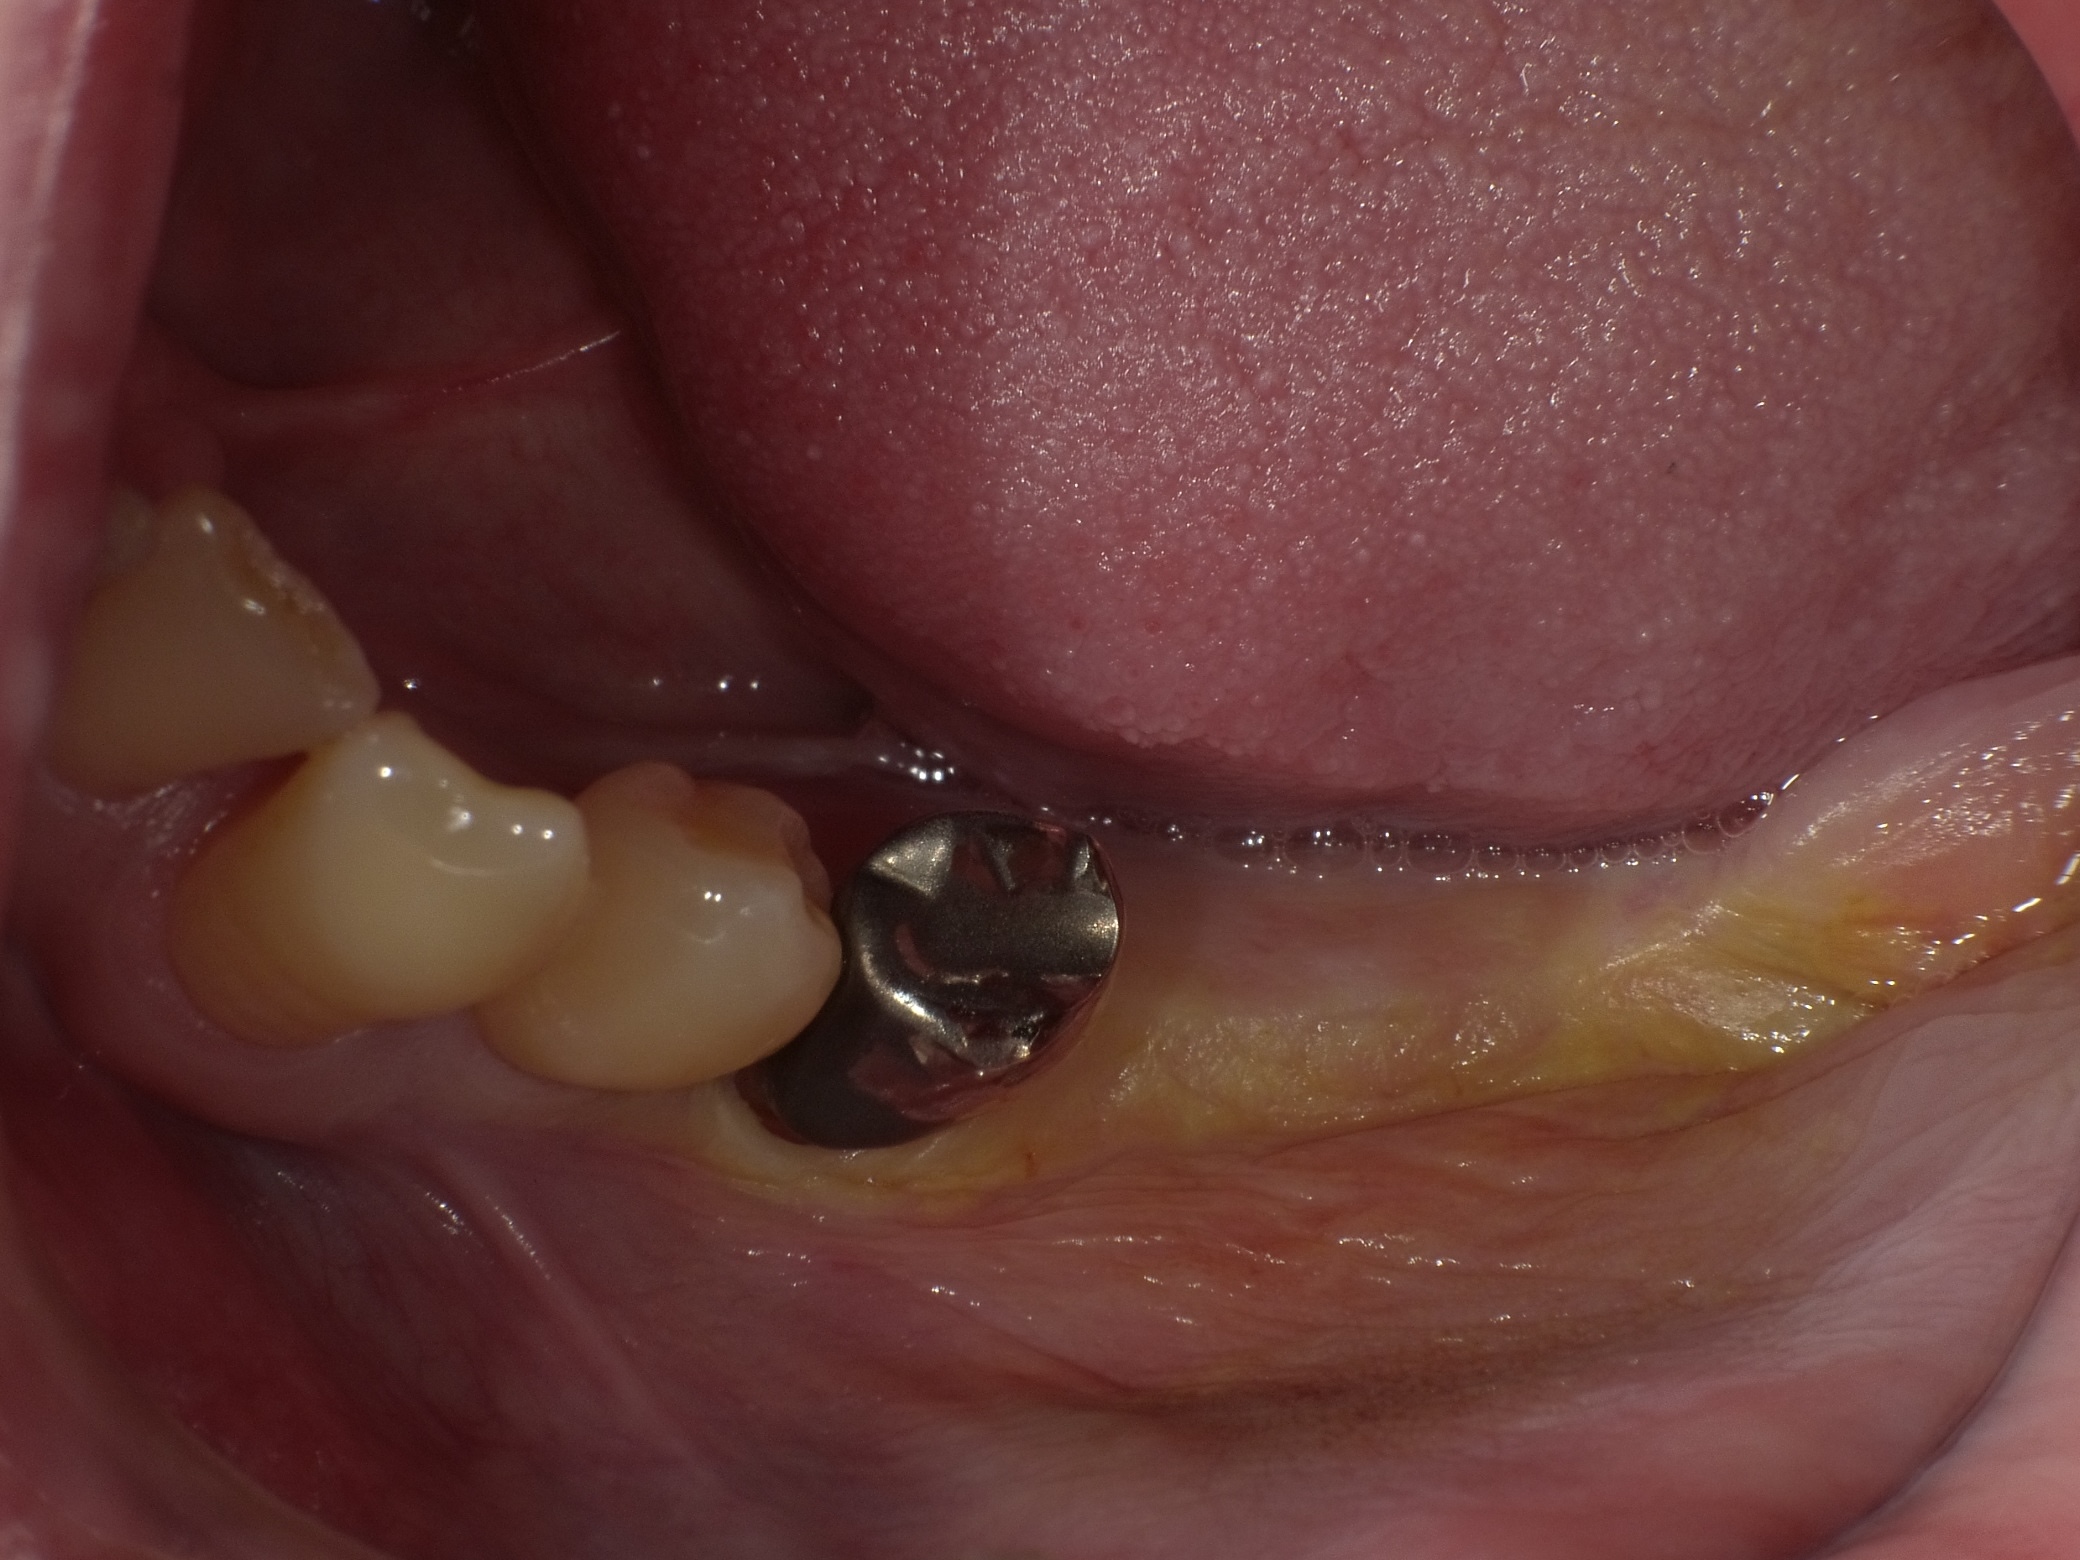

左下2本インプラント症例

主訴 奥歯でしっかり咬めるようにしたい(男性) 治療内容 左下の奥歯2本をインプラントにて治療しています。プラマRFインプラントを埋入。

手術後3ヶ月待ち、骨とインプラントが固まったことを確認し、二次手術後に型取りを行っています。当院では、ほとんどの症例でデジタルでの型取りを行っています。

インプラントを埋入した部位に型取り用のパーツをはめ、3Dスキャナーにて型取りをし、ジルコニアクラウンの被せ物を作製しています。完成後の咬合面は状態を確認後、埋めていきます。

治療期間 約4ヶ月

費用 総額 ¥700,000-(税別) リスクと副作用 ・外科治療となるので、お身体の状態によっては受けれない場合がある(広範囲に適用可能な治療ですが、個々の患者様の状況によって適用外な場合もある)

・術後に多少の痛みや腫れが出ることがある -